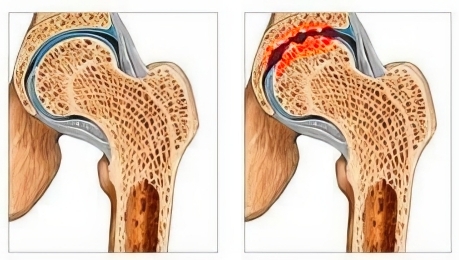

Uitați-vă la aceste imagini, puteți vedea că în imaginea din dreapta nu există un spațiu articular, oasele se freacă una de alta, provocând multă durere. Iar acest proces este foarte greu de oprit!

- Artrita de lungă durată (artrită reumatoidă, tuberculoză articulară etc.). Tulburările metabolice din lichidul sinovial duc la o nutriție inadecvată a cartilajului, încetinesc reînnoirea celulelor moarte și provoacă distrugerea cartilajului.